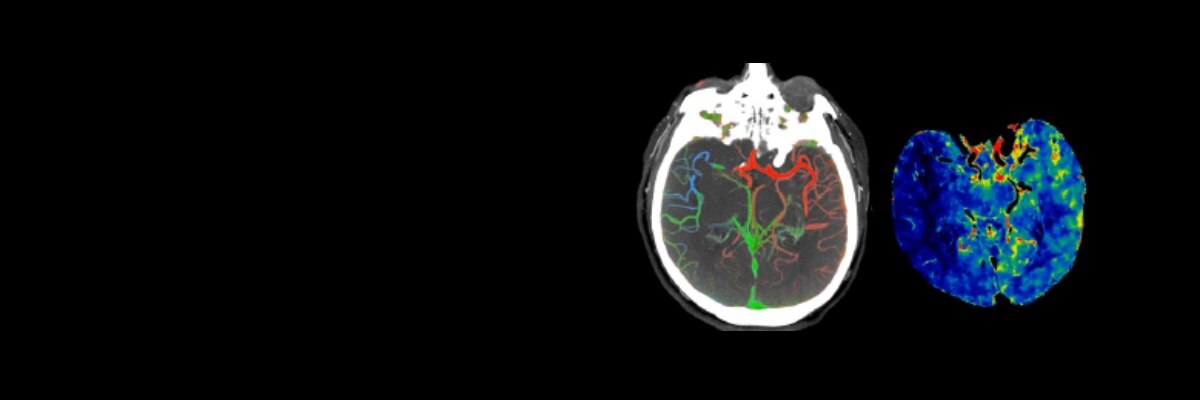

Centricity Open PACS AI Solution

As a radiologist, you have the difficult challenge of not only assessing patient information and providing a differential diagnosis, but also determining which cases to read at any given time. Learn more